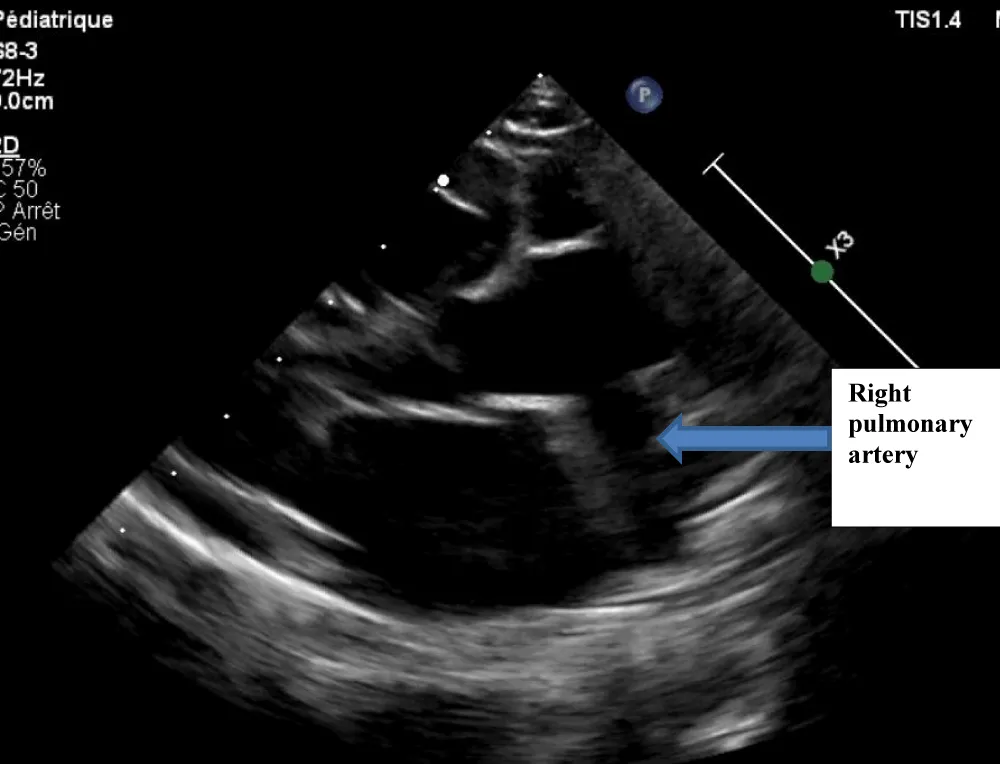

The electrocardiogram showed bi-atrial and left ventricular hypertrophy. On frontal telethorax, cardiomegaly with a supra-diaphragmatic peak, a right inferior arch overhang, and peri-hilar vascular overload, predominantly on the right. Cardiac ultrasound revealed a situs solitus heart with levocardia. The aorta normally emerges from the left ventricle, without obstruction. After a few centimeters, it gave way to a right pulmonary artery that filled correctly in systole without obstruction (Figures 1,2). The left pulmonary artery arises directly from the right ventricle. All cardiac cavities are dilated—suprasystemic pulmonary hypertension with ostium secundum-type atrial septal defect with right-to-left shunt. Cardiac angioscan confirmed the diagnosis, showing a 13 mm right pulmonary artery arising from the aorta. The left pulmonary artery arises directly from the right ventricle and measures 9.73 mm, with a functional pulmonary valve (Figures 3,4). Biological tests revealed microcytic hypochromic anemia at 9.3 g/dl. Medical treatment was based on furosemide, captopril, and spironolactone. A surgical cure after catheterization with reimplantation of the right pulmonary artery was indicated. The child died before surgery.

Figure 1: Echocardiography image showing the Right Pulmonary Artery (RPA) exiting the aorta.